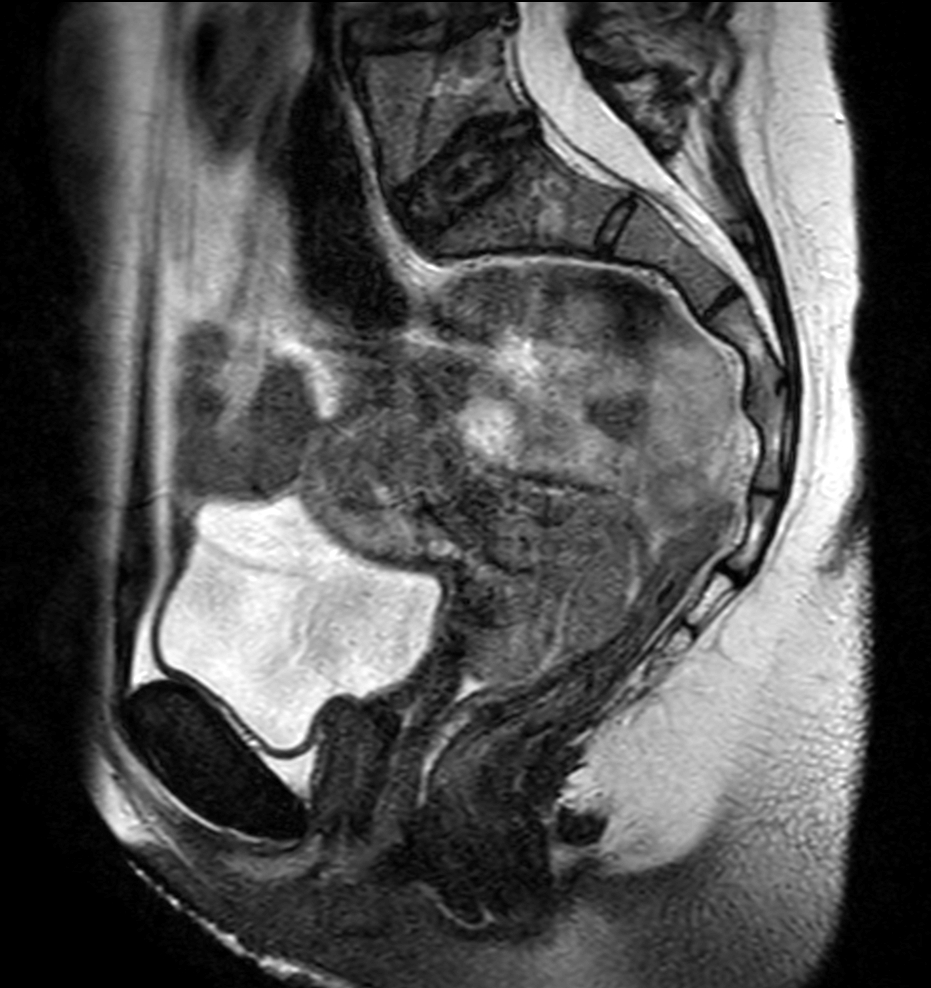

MRI simulation for cervix treatment variable bladder filling state